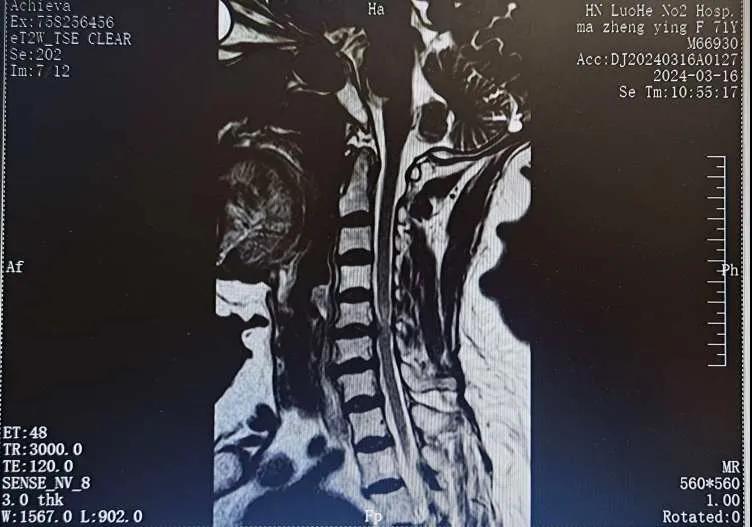

近日,70歲的馬阿姨,因摔傷后出現(xiàn)持續(xù)性頸部疼痛伴右側(cè)肢體無(wú)力、麻痛,影響日常生活。于是來(lái)到市二院神經(jīng)外科就診,經(jīng)檢查發(fā)現(xiàn):頸椎MR示:頸3/4、4/5、5/6、6/7椎間盤變性突出(中央型)并繼發(fā)性椎管變窄,頸椎退行性改變,頸5椎體水平頸髓水腫。神經(jīng)外科副主任劉沛濤根據(jù)患者癥狀、體征、影像學(xué)三者結(jié)合診斷為“脊髓型頸椎病”,考慮到患者癥狀逐漸加重、保守治療效果不佳等情況,建議盡快手術(shù)治療。